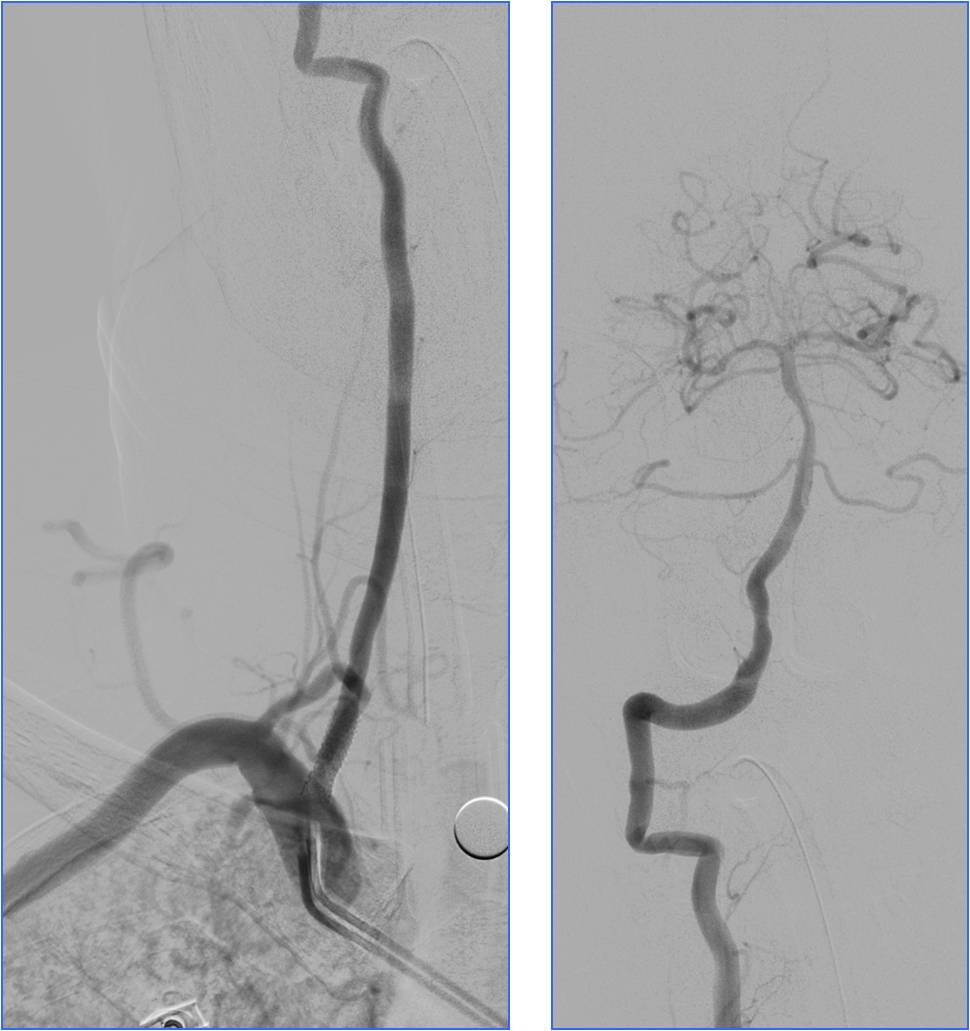

▼左椎动脉颅内段闭塞,脊髓前动脉代偿

▼右椎动脉颅外段闭塞

▼取栓后左椎动脉V4段残留狭窄

▼球囊成形,狭窄改善,不能维持

▼Wingspan支架置入